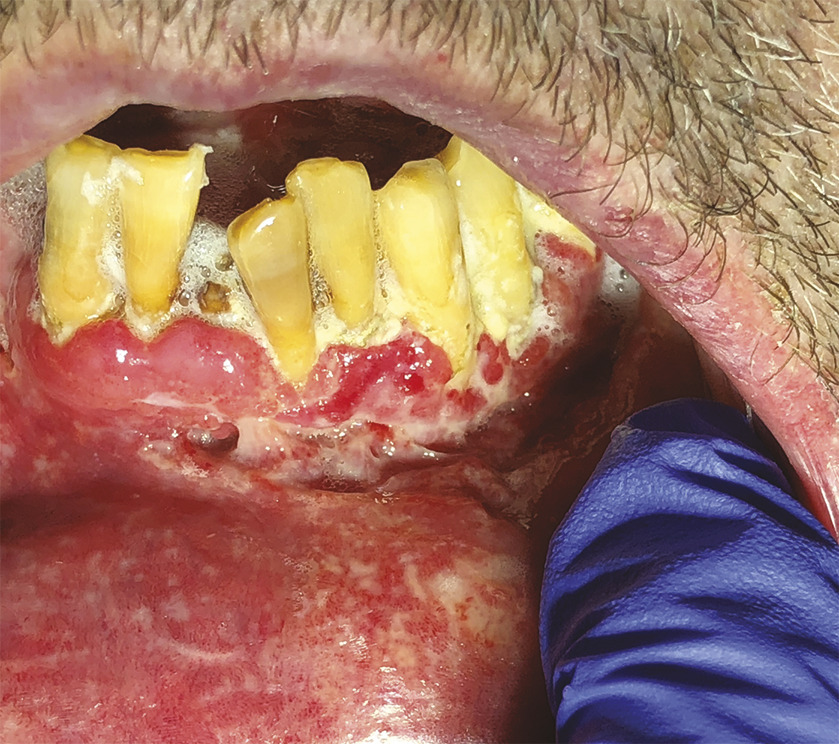

Cet homme de 56 ans vivant avec le VIH et en rupture thérapeutique, était adressé pour une gingivite ulcéro-nécrotique (fig. 1) et des adénopathies sous-mandibulaires bilatérales, évoluant depuis trois semaines. La biopsie a objectivé des granulomes épithélioïdes gigantocellulaires, une nécrose caséeuse (fig 2) et des mycobactéries. L’imagerie thoracique a révélé des nodules pulmonaires évoquant une miliaire tuberculeuse (fig 3).

Le patient a bénéficié d’une quadrithérapie initiale (isoniazide, rifampicine, pyrazinamide, éthambutol), au cours de laquelle les thérapeutiques antirétrovirales ont pu être réinstaurées, suivie d’une bithérapie (isoniazide, rifampicine). Les symptômes oraux ont régressé sous traitement et un contrôle à 4 mois a confirmé une nette amélioration.

Les lésions peuvent être primaires, caractérisées par des ulcérations associées à des adénopathies cervicales, ou plus souvent secondaires, par inoculation directe, via les crachats bacillifères, ou diffusion hématogène. L’atteinte linguale reste la plus fréquente, mais celle du palais, des lèvres et de la gencive s’observe aussi ; l’ulcération est la lésion la plus commune, mais nodules, tuberculomes voire ostéomyélites sont possibles.2